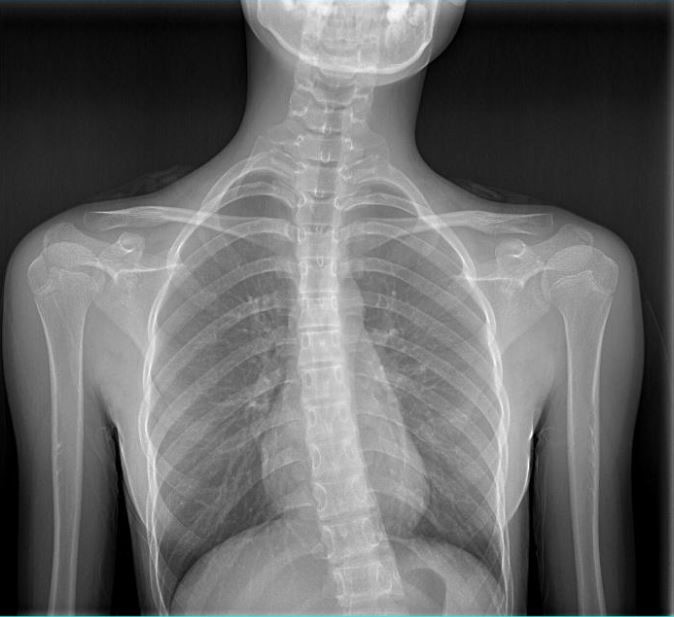

女 16岁

脊柱侧弯畸形

AEC 80KV

脊柱侧弯畸矫形术前检查

通过全景拼接图像可以清晰显示脊柱侧弯的具体细节,为矫形手术提供更详尽的资料。